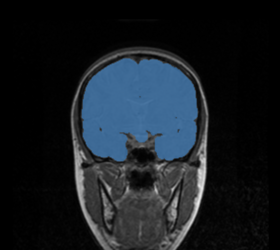

BRAINSMush uses the Maximize Uniformity Summation Heuristic(MUSH) optimizer, as developed at the University of Iowa, to extract the brain and surface CSF from a multi-modal imaging study. It forms a linear combination of multi-modal MR imaging data to make the signal intensity within the brain as uniform as possible. This resulting image is then thresholded to obtain the brain and surface CSF region.

The image is thresholded by the mean signal intensity plus-or-minus five standard deviations.